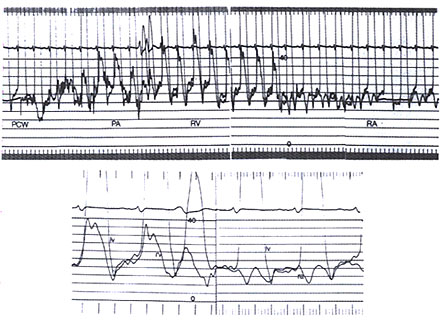

Figure 38 h

Hemodynamic record of a patient with surgically proven constrictive pericarditis. Top. Slow paper speed recording of high-gain left ventricular (LV) pressure and simultaneous right heart pullback from pulmonary capiLlary wedge (PCW) to pulmonary artery (PA), right ventricle (RV), and right atrium (RA). Bottom. Fast paper speed recording of LV and simultaneous RV and RA pressure tracings. Note the increased and equal atriaL and diastolic pressures, the prominent X and V descents on the RA tracing, and the dip and plateau on the RV and LV tracings during longer diastotes.

(Courtesy of Peter j. Engel, MD. From Hoit BD. Pericardial disease and pericardial

heart disease. In: O'Rourke RA, ed. Stein's Internal Medicine, 5th ed. St. Louis, Missouri: Mosby-Vear Book; 1998:273.)